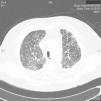

Síndrome de Sweet con afectación pulmonar de evolución fatal

Fatal sweet with pulmonary involvement